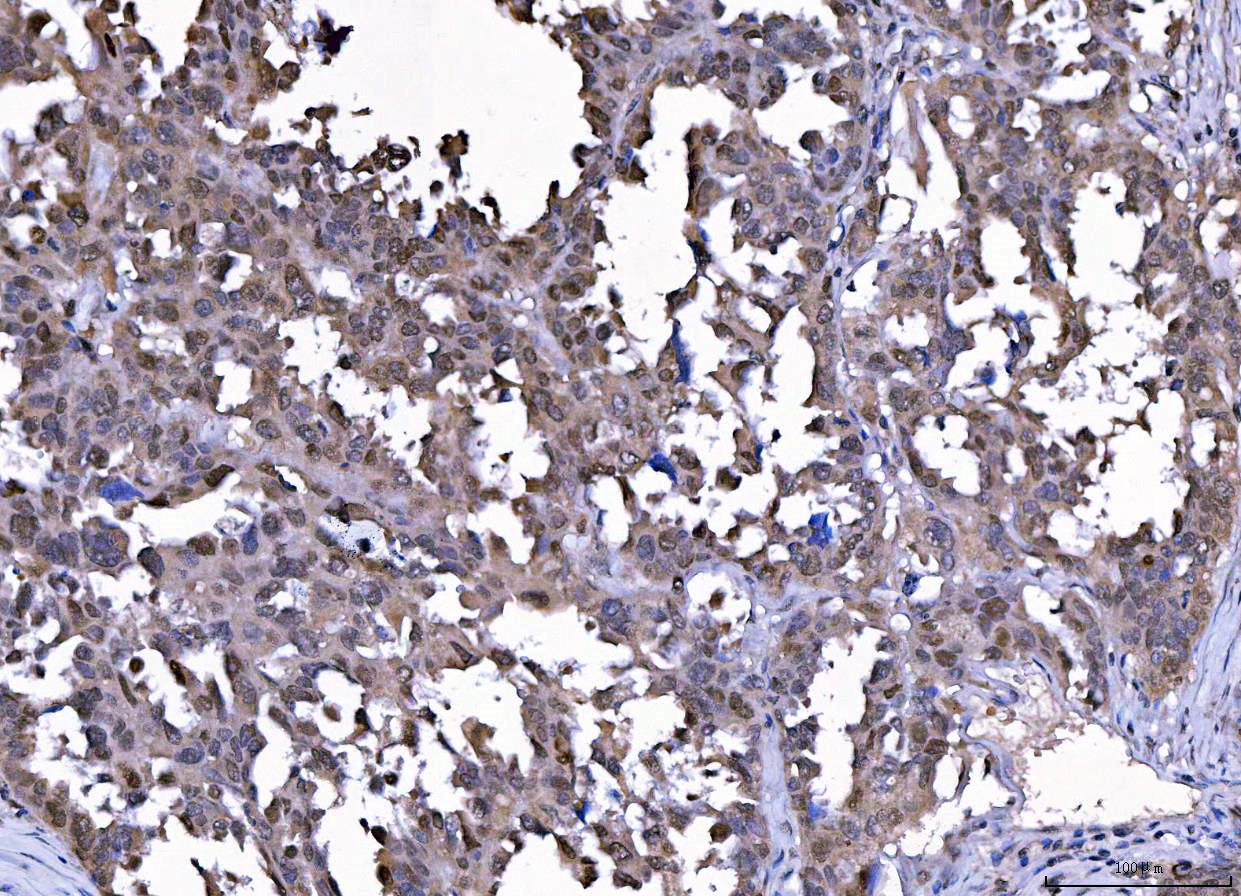

IHC analysis of CDK2 using anti-CDK2 antibody (M00166-4).

CDK2 was detected in a paraffin-embedded section of human renal clear cell carcinoma tissue. Biotinylated goat anti-mouse IgG was used as secondary antibody. The tissue section was incubated with mouse anti-CDK2 Antibody (M00166-4) at a dilution of 1:200 and developed using Strepavidin-Biotin-Complex (SABC) (Catalog # SA1021) with DAB (Catalog # AR1027) as the chromogen.